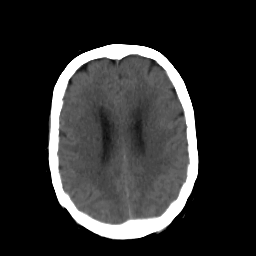

In this study, the dataset introduced in [8], which is publicly available111https://github.com/ChengBinJin/MRI-to-CT-DCNN-TensorFlow, is used for performance evaluation. It consists of 367 paired CT and MR images with the size of 512256. In the original dataset, it is noted that several CT images have stereotactic head frame that was used in Gamma Knife treatment. This head frame manually removed from the CT images. In addition, there exist various CT and MR slices that brings incredible difficulty in training the generator. Therefore, 100 images are selected from similar slices for each modality, in which 90 and 10 images are used for training and testing, respectively. Fig. 5 shows four examples of pre-processed samples.